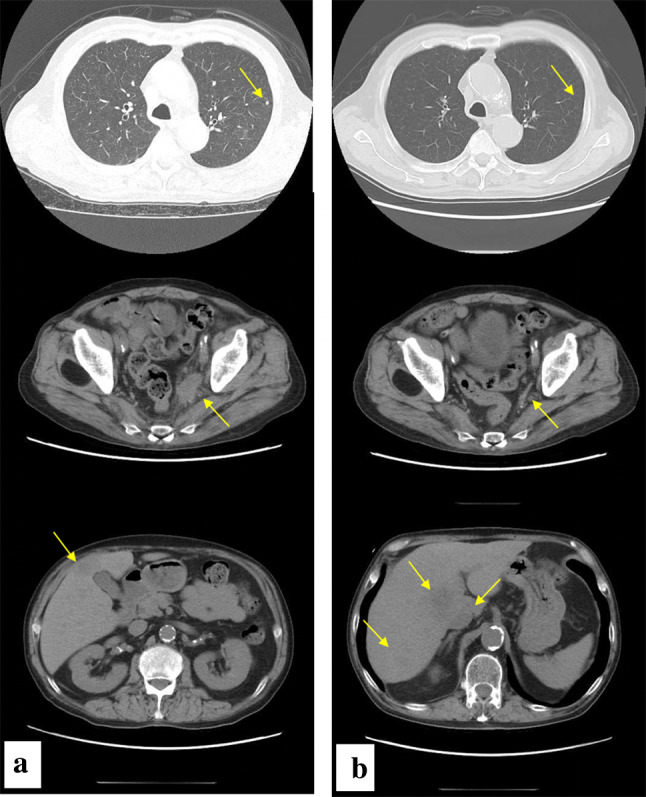

Fig. 2.

Neck ~ pelvic computed tomography before (a) and after (b) chemotherapy with irinotecan and cisplatin; Pulmonary metastases (arrows) disappeared. Metastases to pelvic lymph nodes (arrows) were reduced in size. Hepatic metastases (arrows) increased in number and size